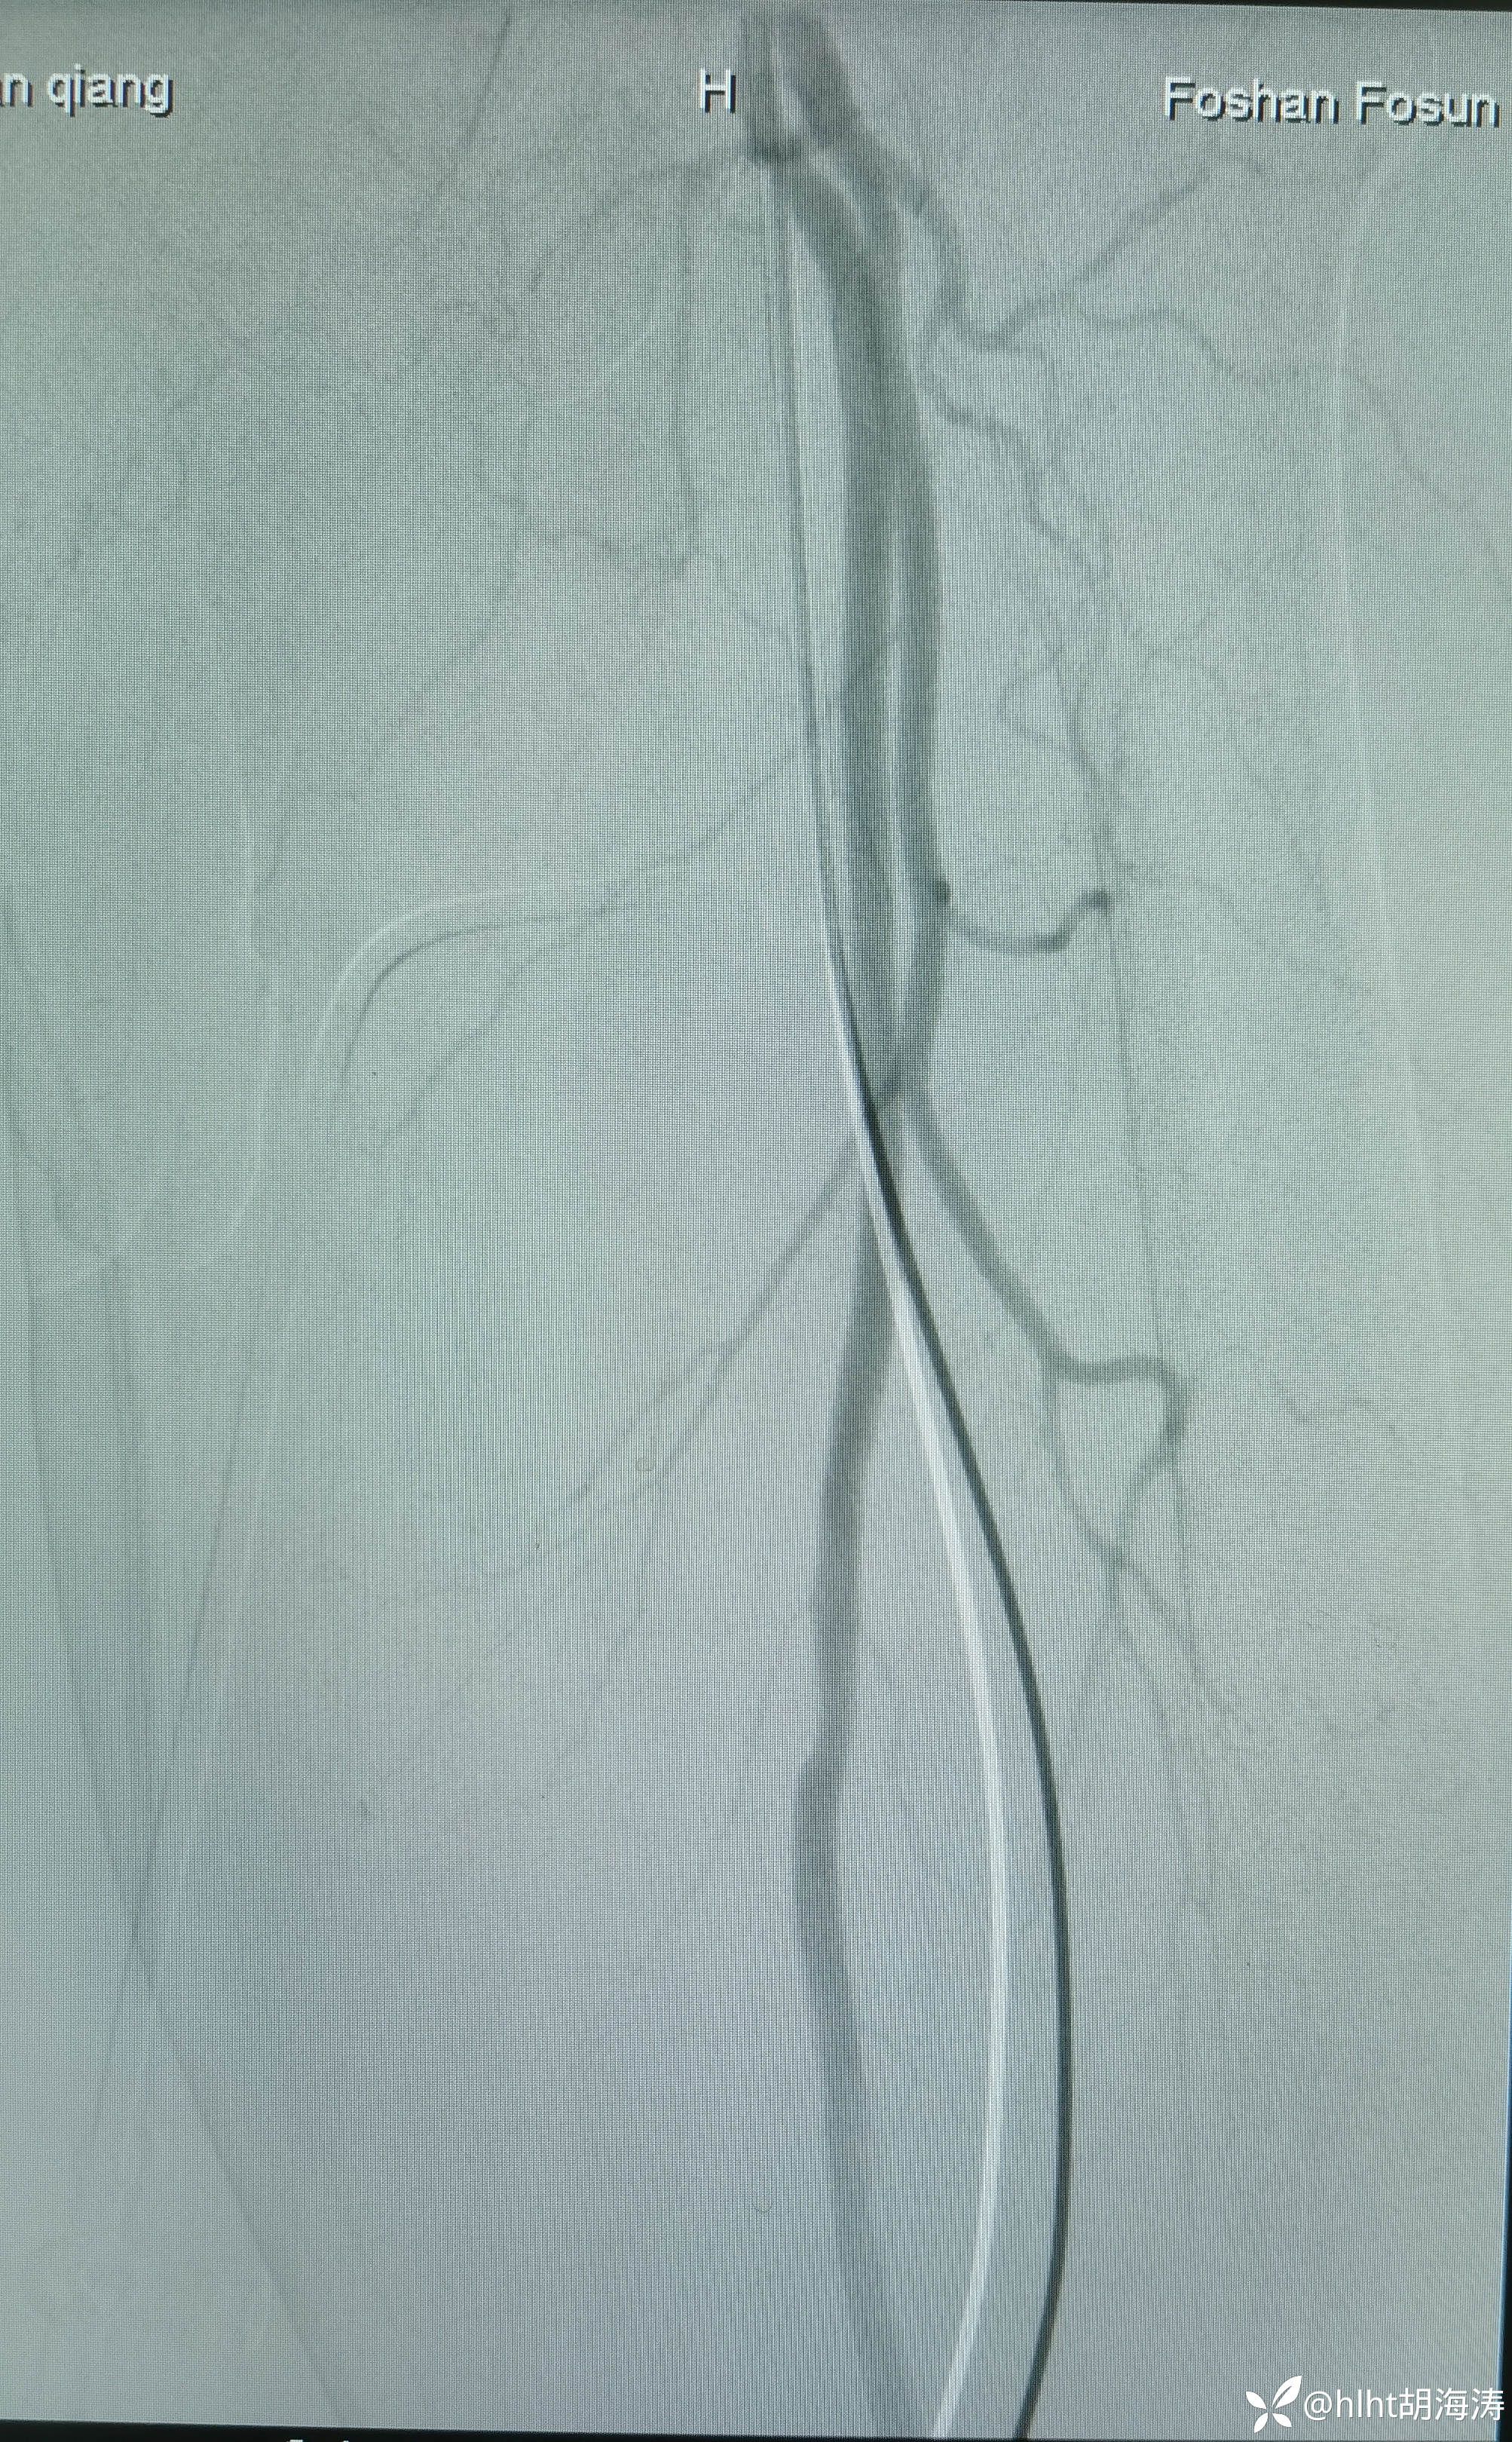

多次尝试,翻山,导丝没法进入左髂外,然后右侧腹股沟区穿刺:微创针

置入5F血管鞘:造影提示右侧髂外开口处重度狭窄

右侧髂外动脉直径不到左侧的1/2,扩到5mm,血流好,无限流夹层

右侧股浅很细,中远段闭塞导丝没法过,考虑髂外通了,循环也会改善: